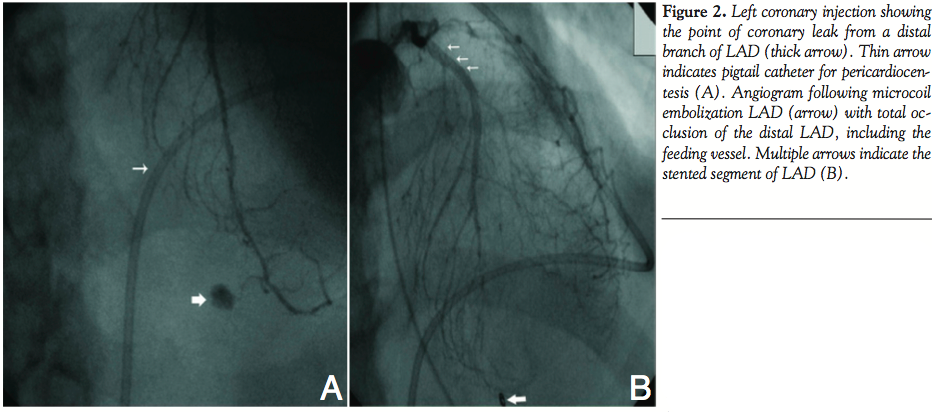

RCA angioplasty. The right coronary artery was engaged with a 6 Fr Judkins right guide catheter, and the lesion was directly stented using 3.5 mm x 18 mm bare metal stent at 14 atm pressure with acceptable result. Immediately after shifting to ICCU, the patient developed chest pain with hypotension, and ECG revealed pericardial effusion with cardiac tamponade. Pericardiocentesis was started and coronary angiogram showed contrast leak from a tiny distal branch of LAD (Figure 2A). Retrospective review of angiogram revealed that the guidewire was sitting deep

into the same branch during LAD angioplasty. Prolonged balloon inflation at the origin of the culprit vessel did not yield satisfactory result. Therefore, we decided to perform microcoil embolization of the distal LAD. A MiraFlex microcatheter (Cook) with inner diameter of .021-inch was positioned near the origin of the feeding vessel and embolization was performed using an 18-2-2 MCWE HILAL microcoil (Cook). The result was total occlusion of the distal LAD including the culprit branch (Figure 2B). The patient experienced angina of moderate severity, which subsided gradually. About 6 H later, he developed hypotension and echocardiogram revealed re-accumulation of pericardial fluid with evidence of cardiac tamponade. The patient was shifted to the catheterization laboratory, and left coronary angiogram confirmed total occlusion of the distal LAD, and no evidence of reopening of the coronary leak. Pericardiocentesis was continued, which showed aspiration of fresh blood, indicating ongoing bleeding into the pericardial cavity. Therefore, RCA injection was also performed to rule out any leak from the right side. To our surprise, a marginal branch of the RCA was seen supplying the same culprit vessel on left through collateral causing continuous loss of blood (Figure 3A). Selective microcoil embolization of the marginal branch using 18-2-2 MCWE HILAL microcoil (Cook) could successfully close it, resulting in total cessation of blood loss (Figure 3B). Recovery of the patient was mostly uneventful except for transient elevation of serum creatinine level.